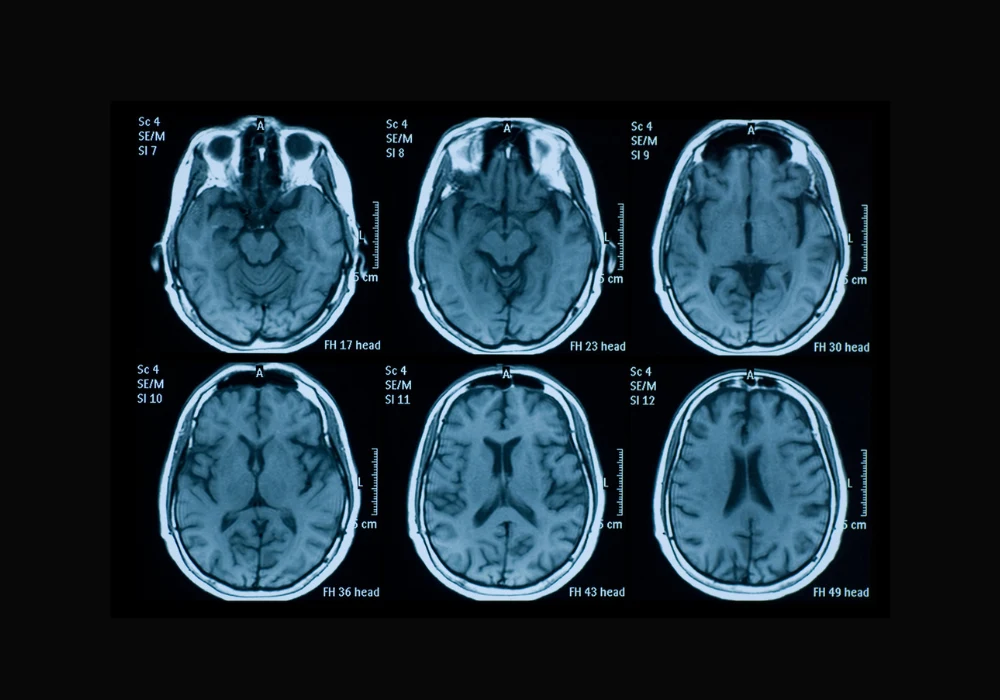

Acute ischemic stroke (AIS) remains a major cause of death and long-term disability. Timely imaging and accurate analysis of brain lesions are critical to predicting functional recovery and guiding clinical decision-making. Traditionally, infarct size has served as a principal radiologic marker, but it offers only moderate predictive power, especially in cases involving small infarcts. Chronic brain changes, such as white matter hyperintensity (WMH), add complexity to outcome prediction but are inconsistently quantified in practice. Addressing these challenges, a multilabel deep learning segmentation model has been developed to analyse acute and chronic brain lesions using multisequence MRI. This model aims to enhance short-term prognosis prediction after AIS by integrating radiologic features with clinical variables.

Manual segmentation of stroke lesions is laborious, subject to inter-reader variability and limited in scalability. The newly developed convolutional neural network (CNN), based on the SegResNet architecture, enables automated multilabel segmentation of both acute infarcts and chronic WMH from multisequence MRI inputs, including FLAIR, diffusion-weighted imaging (DWI) and ADC maps. The network demonstrated strong segmentation accuracy across training, validation and testing datasets, with Dice coefficients of up to 0.95 for infarct core and 0.92 for WMH. This performance suggests the model's capability to distinguish between overlapping hyperintensities, a task that often confounds manual analysis. By providing detailed quantification of infarct volumes and WMH distribution, the model offers a more nuanced view of cerebral damage, which is crucial for comprehensive outcome prediction.